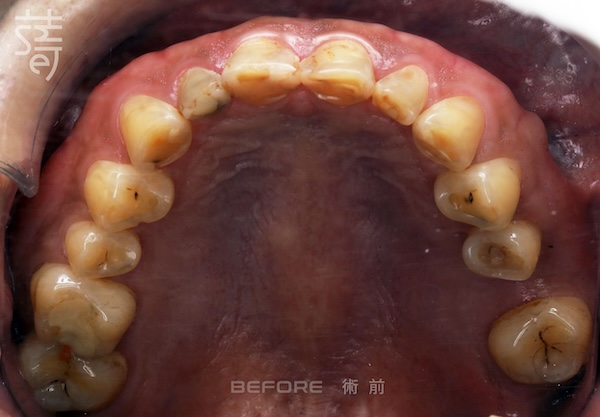

三十多歲的李先生就是典型例子。多年磨牙讓牙齒幾乎磨平,加上後牙缺失、牙齒傾倒,導致越咬越深。長期下來,不僅口腔功能受限,也讓他這位經常需要上鏡的專業人士,在鏡頭前漸漸失去自信。

Mr. Li, in his thirties, is a textbook case. Years of grinding had flattened his teeth, while missing and tilted molars worsened the bite. Over time, his oral function suffered, and as a professional frequently on camera, he gradually lost confidence in front of the lens.

第一階段:隱適美矯正 Stage One: Invisalign Alignment

將牙齒重新排列整齊,調整上下咬合,把原本傾倒的第二大臼齒推回正確位置,為後續植牙和假牙重建打好基礎。

Teeth were realigned, the bite adjusted, and the previously tilted second molars repositioned, laying a solid foundation for implants and prosthetics.